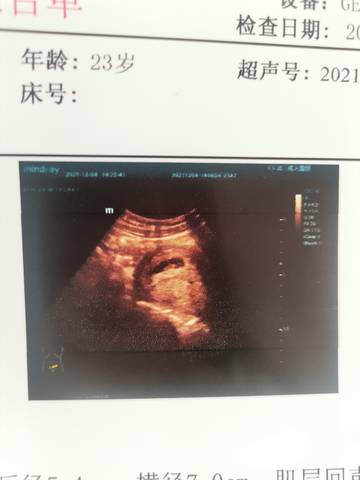

journal_insert_pic_1673509929journal_insert_pic_1673509950

亲爱的,图片里面的这个图片显示出来的话,只要孩子发育好就行了呀,反正你自己多注意,大部分是没事的。